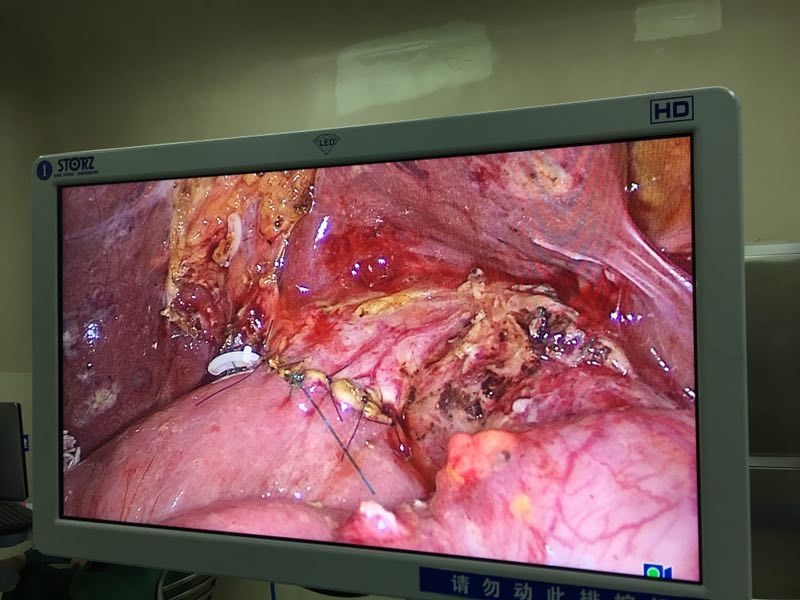

石某某,因突发上腹痛疼痛10小时入院。入院时完善急诊血常规、生化、肝功能、胰代谢以及肝胆脾增强CT等检查,考虑诊断“急性胰腺炎;胰腺假性囊肿”,进一步完善磁共振平扫+MRCP检查,确诊为胆总管囊状扩张症(Ia、C-P型)并发急性胰腺炎。首先进行胰腺炎治疗,予以禁食禁饮、抗炎、护胃、补液、抑制胰腺内外分泌、通便等治疗。经积极治疗,病情稳定后,复查生化相关指标恢复正常,王文儿主任指示:完善术前相关评估,有限期手术指征,无明显手术禁忌,于4月16日在麻醉科及护理工作人员的积极配合下成功完成全腹腔镜下胆总管囊肿剥除+胆囊切除+胆肠内引流术,术中于胆肠吻合口后方放置一18#引流管,术中生命体征平稳,术中失血量约50ml,手术历时约4.5小时,麻醉复苏成功后安返病房。

术中效果